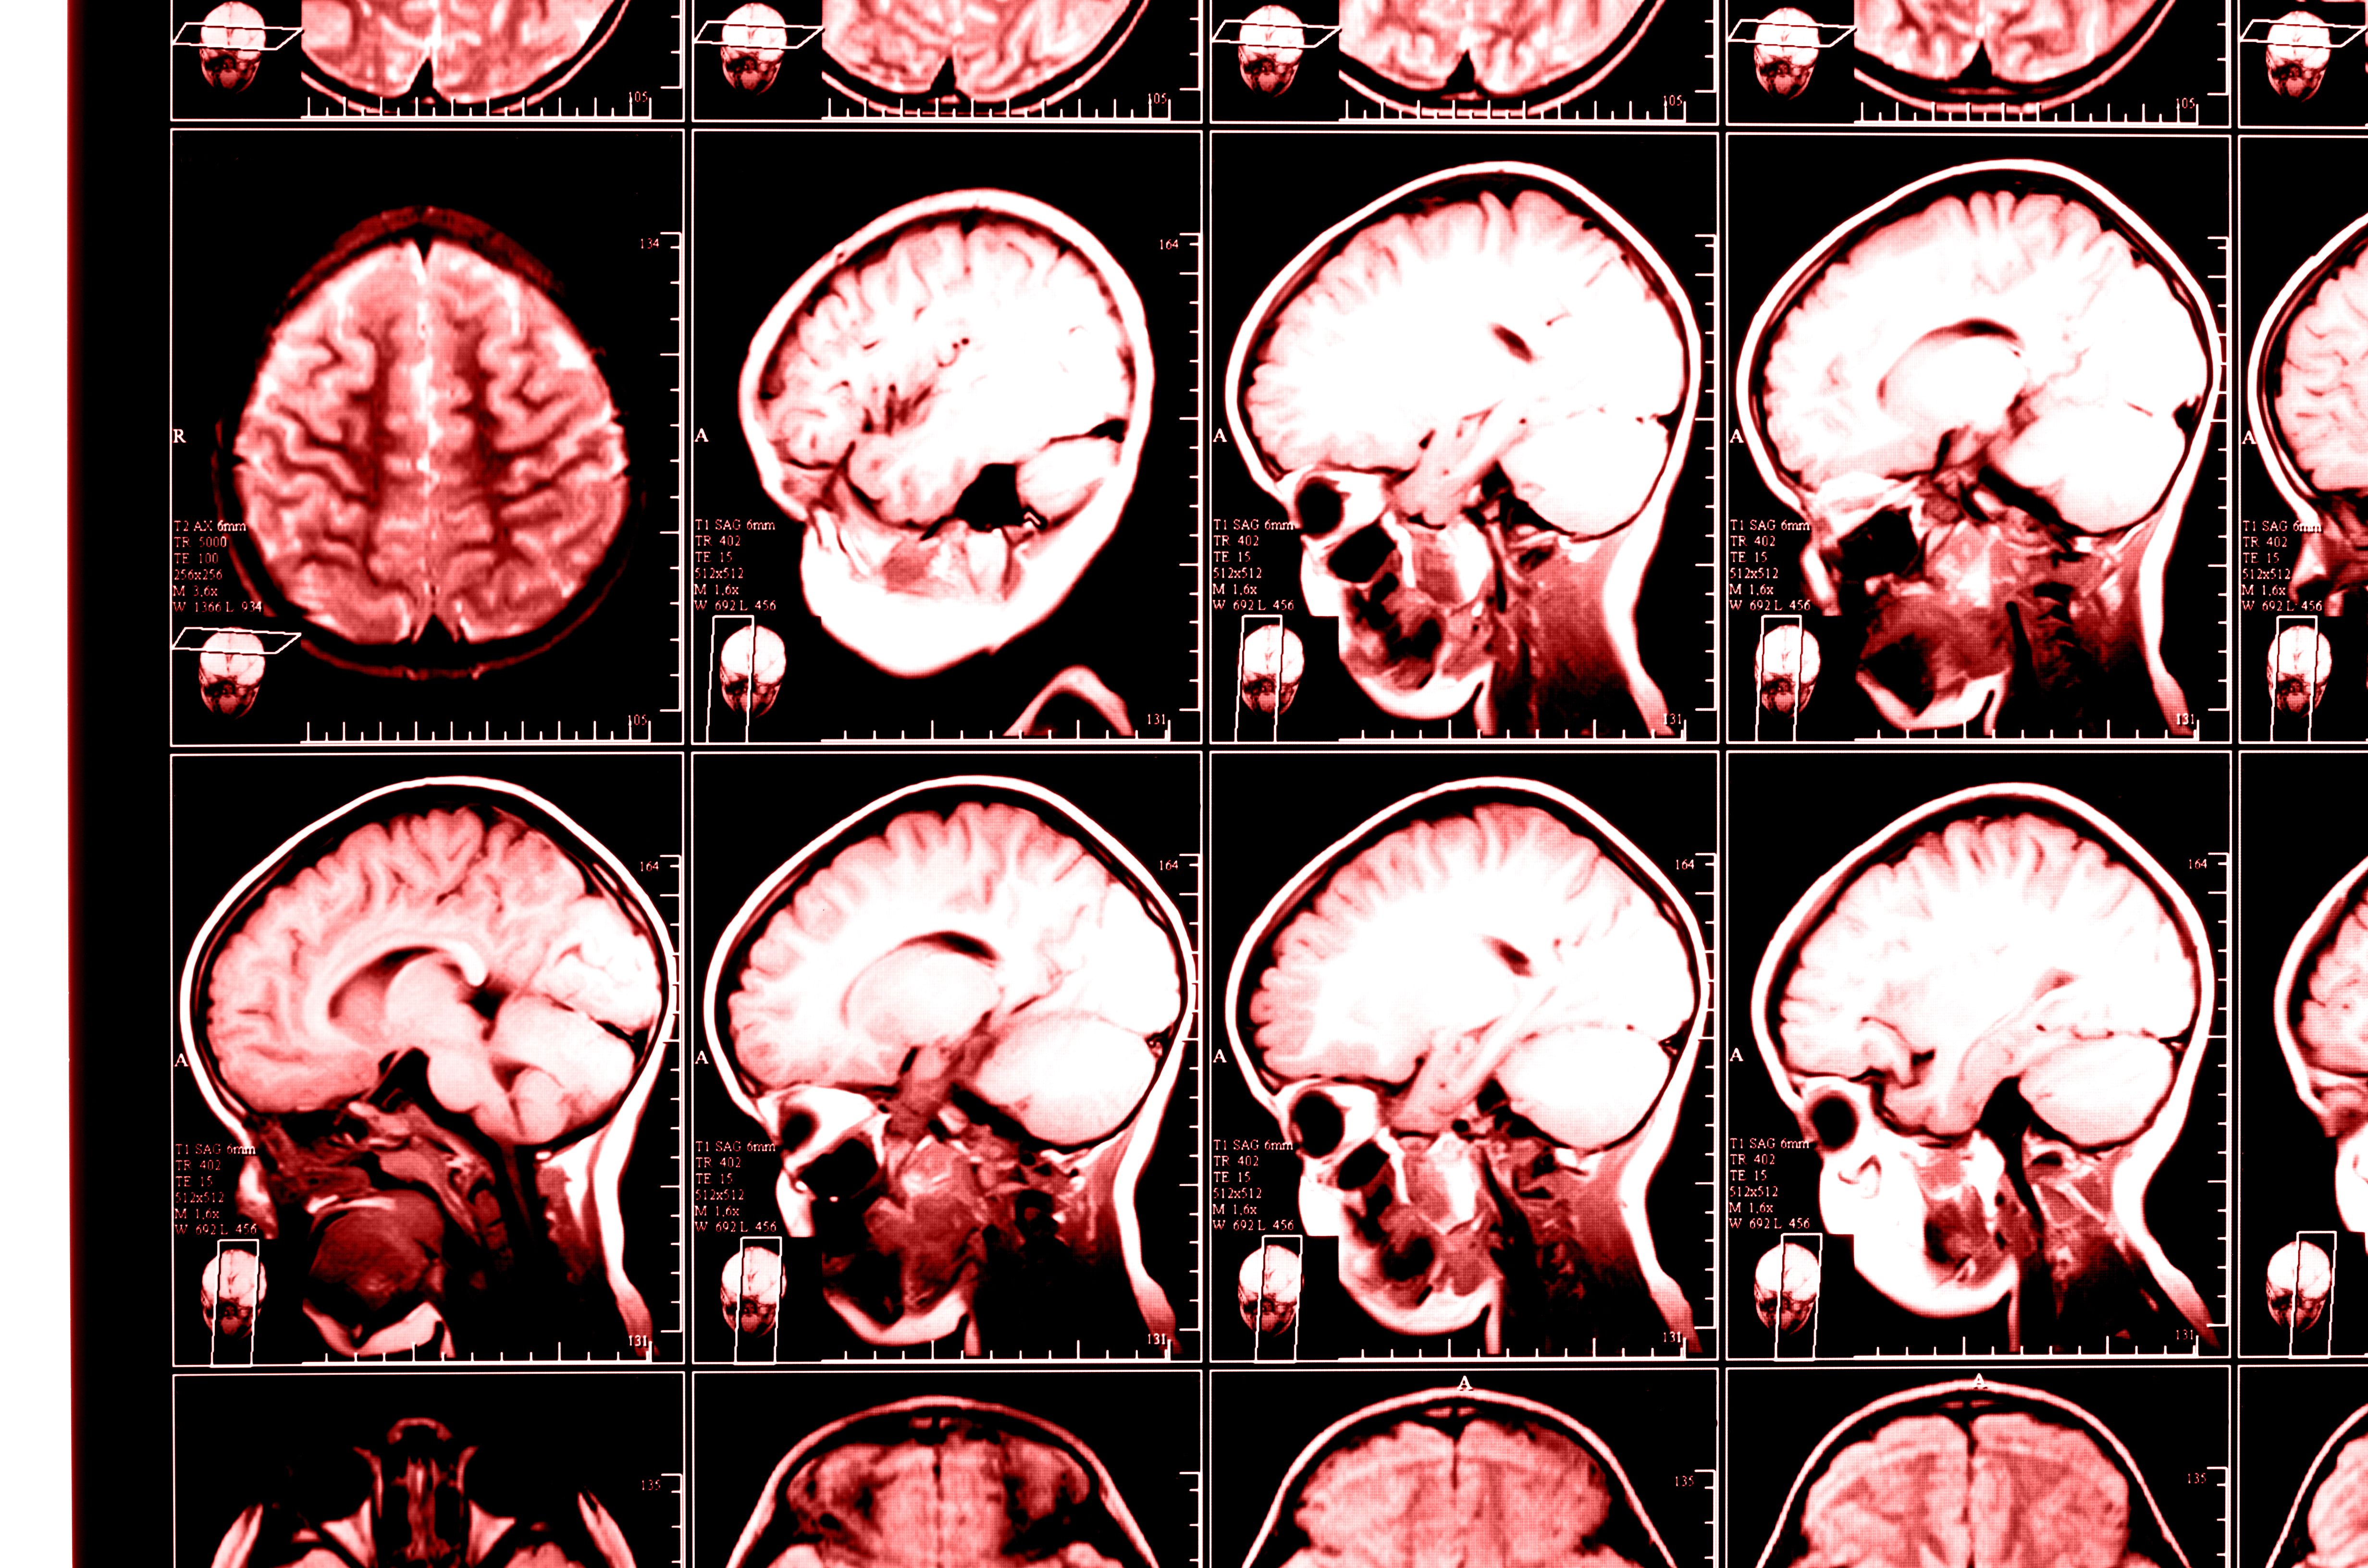

What Is a Traumatic Brain Injury?

A traumatic brain injury (TBI) refers to varying degrees of damage to the brain.